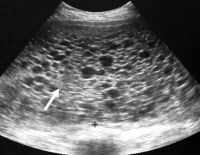

Siêu âm buồng trứng có thực sự cần thiết cho nữ giới?

Siêu âm buồng trứng là một trong những phương pháp được nhiều người lựa chọn khi đi khám phụ khoa. Kỹ thuật này giúp nữ giới phát hiện được nhiều bệnh lý nguy hiểm liên quan đến buồng trứng, tử cung. Tuy nhiên, nhiều người...